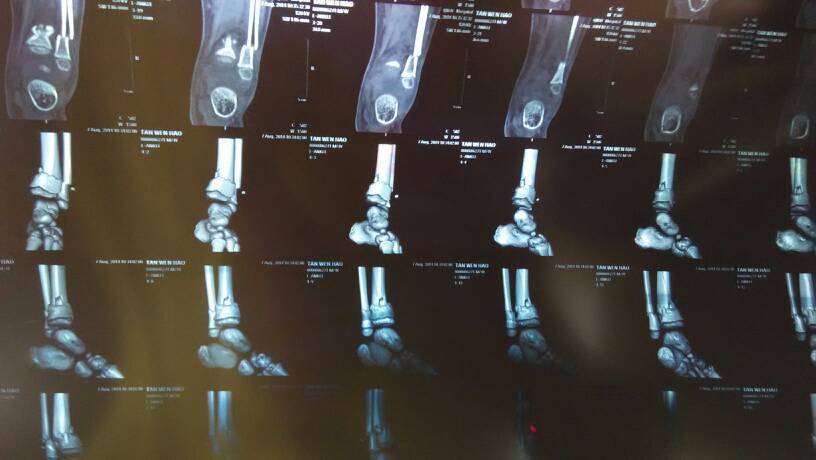

急急急!!!麻烦骨科的大夫都来帮忙看一下。8月4号晚上7点多小孩一个人在家翻窗户摔下了一楼,我们是住在三楼,过程是这样的,小孩是从三楼掉到二楼,二楼外面有个晾衣架,三根铝钢管的那种,因为反冲的作用,然后再从二楼掉一楼的,孩子左额受皮外伤,左腿骨折,属于粉碎性的!当时马上打120把孩子送去了医院,做了该做的检查,包扎了伤口,缝了线,给左腿打了石膏,也留院观察了48小时,无大碍,出院转院了。小孩是男孩,4岁半,!现在问题是腿部骨折很麻烦,目前在医院住院,后天(星期一)手术,主治医师的方法是打两块钢板,手术过程中如果不行还需要打两颗钢钉,以后看恢复,如果恢复的好就快,反之可能会有后遗症,需二次手术!想到孩子这么小,打钢板行吗?请求骨科大夫帮忙看下片子,到底应该如何治疗?跪谢,只有这么点分数,全献上!